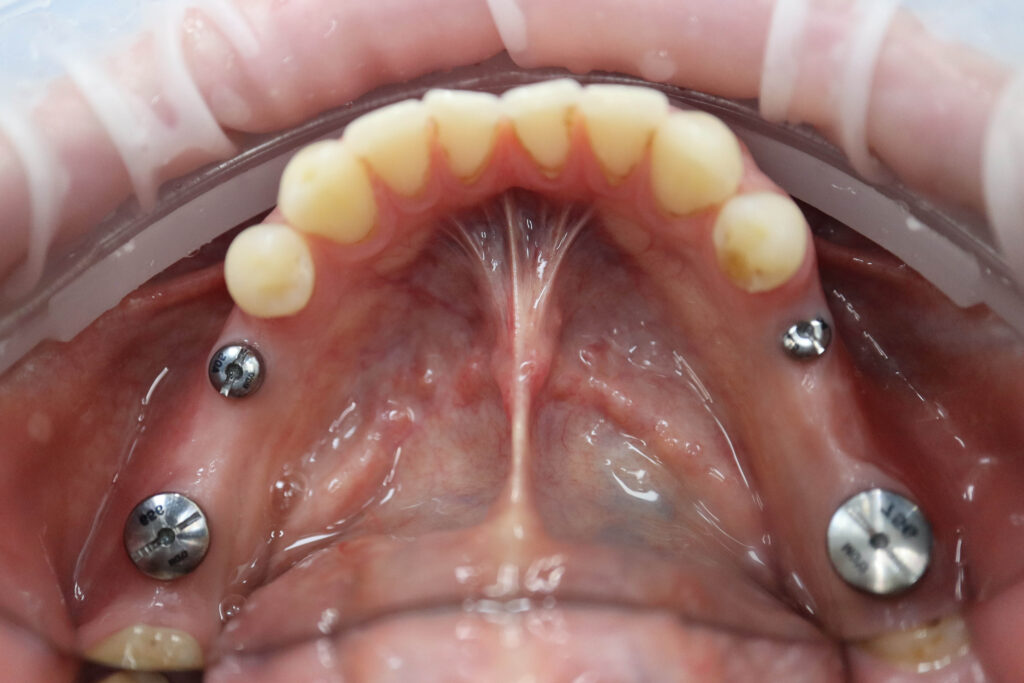

Ситуация до лечения

Пациент обратился с жалобами на эстетические недостатки.

Диагноз: Частичная адентия

Ситуация до лечения Бутримович